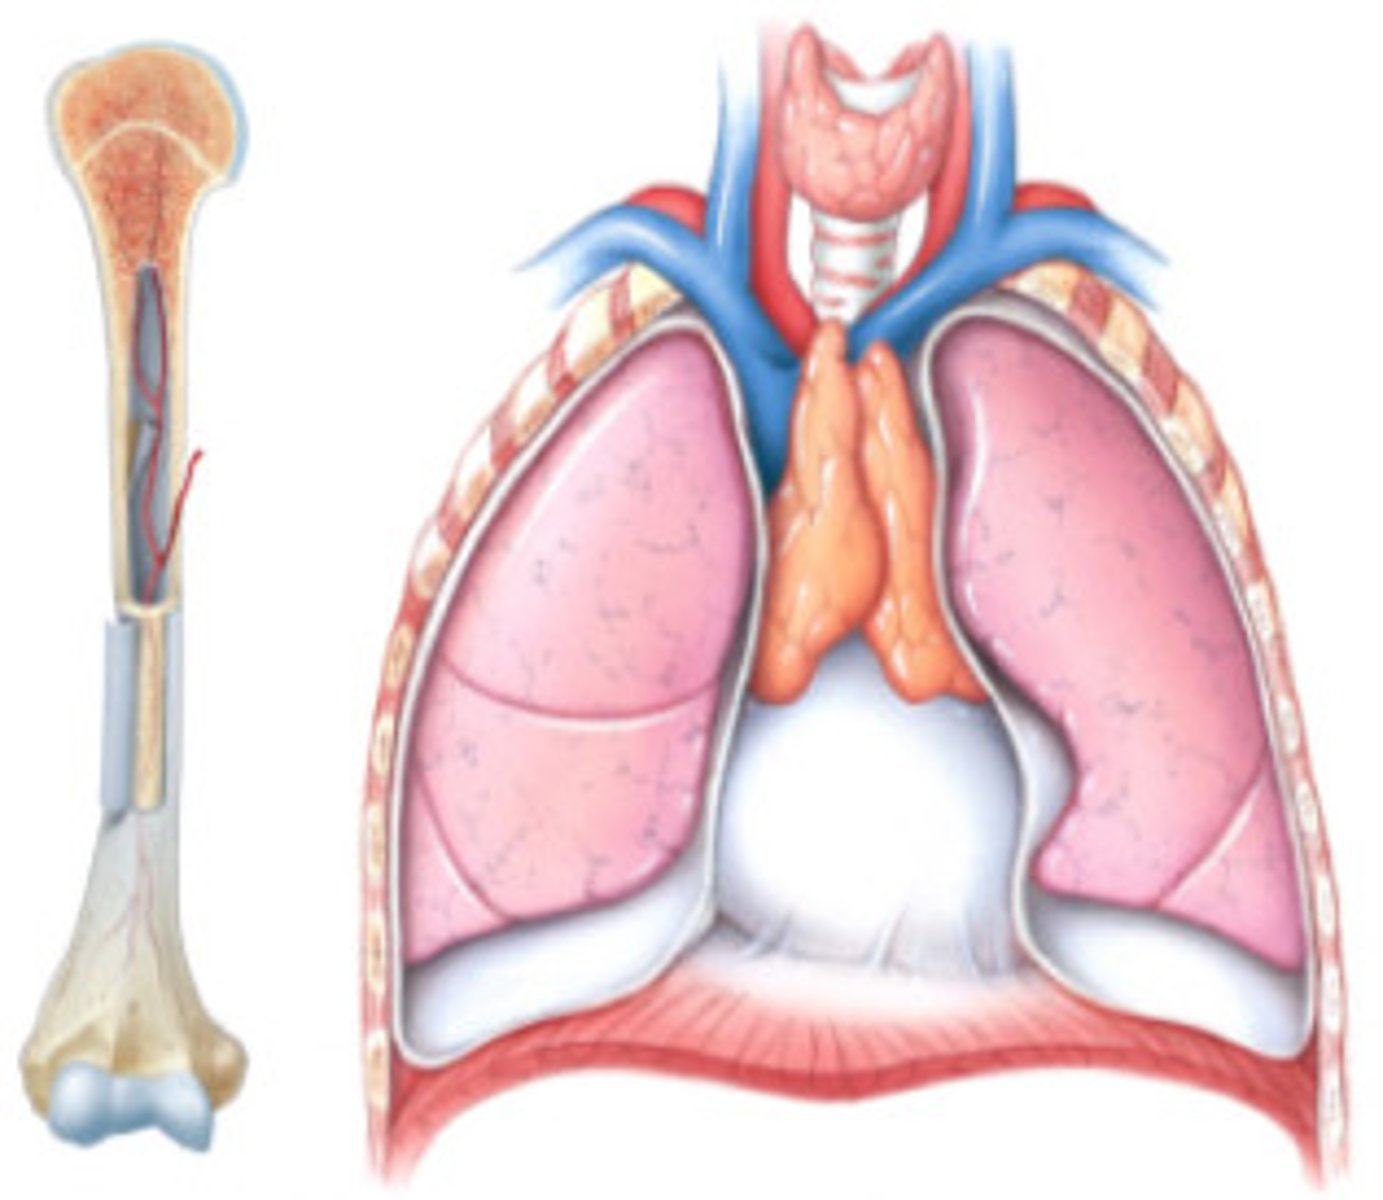

Primary lymphoid tissues

Bone marrow and thymus

What does the bone marrow do?

Produces blood cells

What does the thymus do?

Site of T cell differentiation and maturation

Hematopoiesis

The formation of blood cells from stem cells in the bone marrow